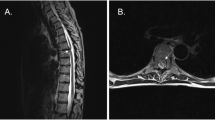

Results: The clinical findings and MRI showed a good correlation. The Horner's syndrome was confirmed with a 4% cocaine test. The patient received a conservative treatment with high-dose steroid therapy (NASCIS-3).

Conclusion: The patient presented with Brown-Séquard syndrome and Horner's syndrome. Clinical examination and MRI made a quick and correct diagnosis. The patient recovered completely after the conservative treatment.